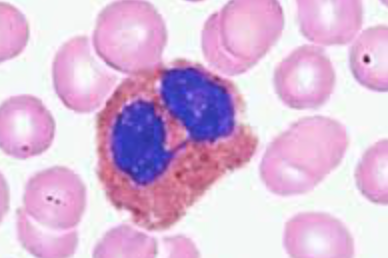

Monocyte

[Function of a] Monocyte

Develop into macrophages in tissues and phagocytize pathogens or debris

Order of Leukocytes from most numerous to least numerous

Neutrophil --> Lymphocyte --> Monocyte --> Eosinophil --> Basophil

(Never Let Monkeys Eat Bananas)